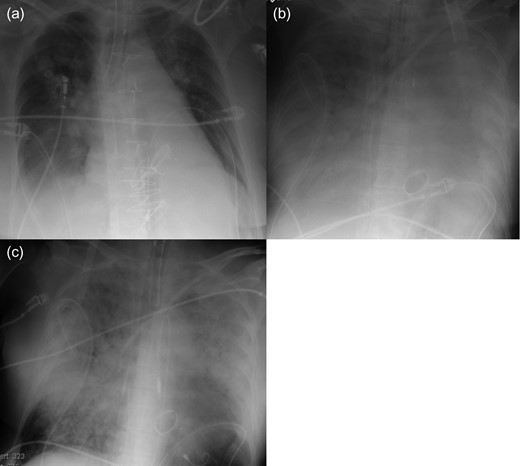

A 66-year-old woman experienced acute dyspnea and was admitted to a regional hospital. Echocardiography revealed severe MR with prolapse of the posterior leaflet. Acute coronary syndrome was ruled out by coronary catheterization. Her condition worsened on Day 2, when she needed a short period of cardiopulmonary resuscitation (CPR). After CPR, the patient was still in severe CS. Therefore, she was transferred to our hospital on the same day. ECLS was immediately implanted percutaneously through the right femoral vessels. Thereafter, her condition stabilized. Ten days after ECLS implantation, surgery including mitral valve replacement, annuloplasty of the tricuspid valve and closure of a giant atrial septum defect was performed. At the operation, an attempt to wean from the ECLS was done, but remained unsuccessful due to right heart failure. After surgery, multi-organ failure (MOF) with massive PE slowly developed (Fig. 2a and b). The Impella system was implanted percutaneously through the left femoral artery on postoperative Day 8 for direct unloading of the LV to treat PE; after implantation, PE showed clear regression on chest radiography (Fig. 2c). Flow from the Impella system was 2.0 l/min, whereas flow from ECLS remained unchanged at 5.5 l/min. Despite her higher systemic output, her general condition had worsened. She died 2 days after Impella implantation due to MOF.

Radiography of Patient 2. (a) After open heart surgery. (b) Before Impella implantation. (c) Two days after Impella implantation.